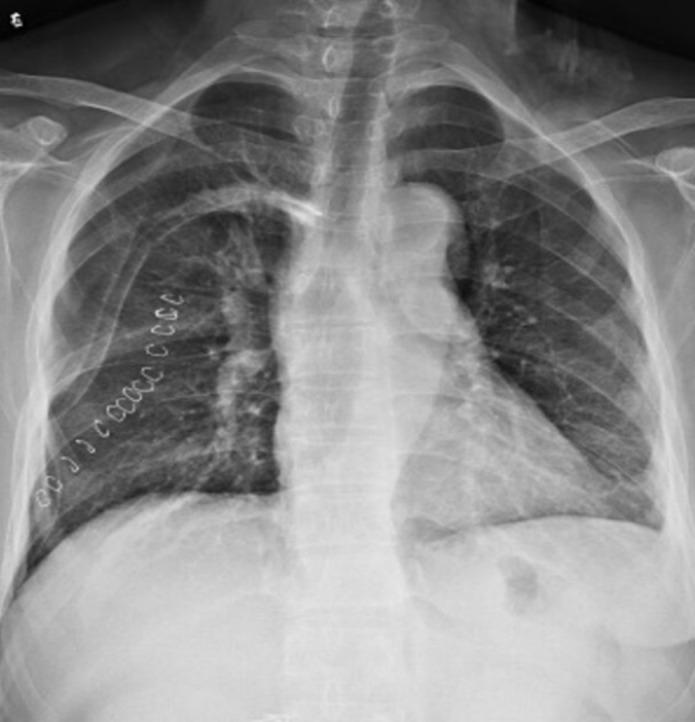

We report a rare case of fibrocystic osteitis associated with a parathyroid adenoma, which was discovered by chance due to a rib tumor. Abnormally elevated serum parathyroid hormone and calcium ion were found before surgery. We suspected primary hyperparathyroidism, and color Doppler ultrasound suggested the presence of a thyroid mass. With informed consent by the patient and her family, we first removed the rib tumor, and one week later, resection of the parathyroid adenoma and thyroid mass was performed on both sides, and the patient recovered well after surgery.

我们报告1例与甲状旁腺腺瘤相关的纤维囊性骨炎罕见病例,该病例因肋骨肿瘤偶然发现。术前发现血清甲状旁腺激素和钙离子异常升高。我们怀疑为原发性甲状旁腺功能亢进,彩色多普勒超声提示甲状腺有肿物。在患者及其家属知情同意后,我们首先切除肋骨肿瘤,1周后双侧切除甲状旁腺腺瘤及甲状腺肿物,术后患者恢复良好。